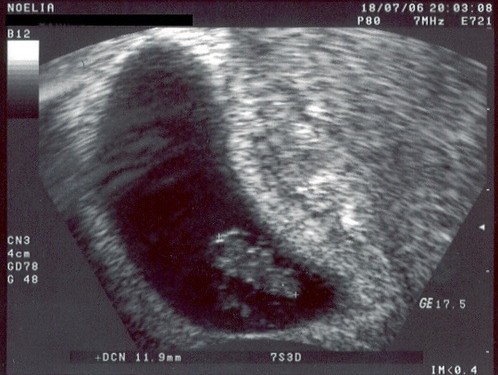

Estas medidas no hacen más que respaldar la marginalidad del procedimiento de aborto terapéutico y el sostenimiento de un doble discurso social: por una parte se dice que es innecesario legislar puesto que el procedimiento se realiza de igual forma (recordemos que en términos concretos TODA interrupción de un embarazo es un aborto, por lo que el procedimiento en caso de embarazo tubario, ectópico, también lo es), pero al no contar con la legislación las mujeres quedan sujetas a decisiones de terceros, ya sea el Estado o un equipo médico, quienes determinarán si el embarazo debe llegar a término o no, pese al sinfín de argumentos significativamente válidos que cada mujer pueda tener.

A no engañarse. En Chile por ejemplo se dan unos 4000 casos anuales de embarazos tubario donde es necesario extraer la trompa para salvar la vida de la madre (teniendo como efecto indirecto e inevitable la extracción del feto), sin que nadie hasta la fecha, tras mas de 20 años de “penalización”, haya sido procesado y condenado (hablamos de casos registrados y documentados en fichas clínicas, no de clandestinidad).